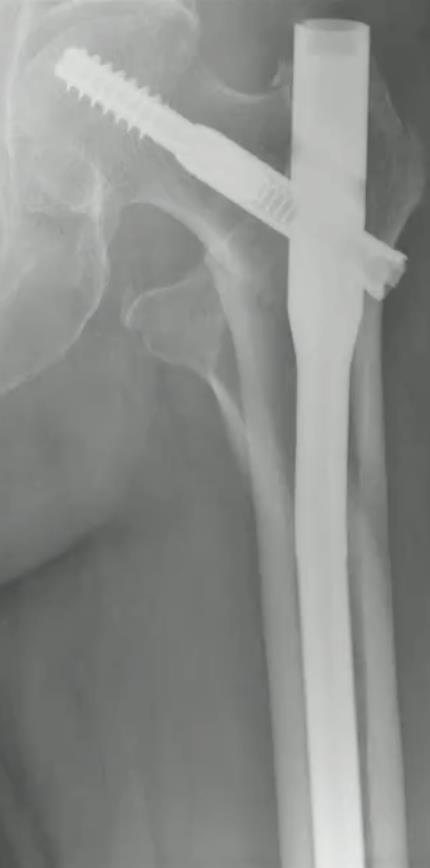

Trochanteric Nail System

• Intramedullary fixation is standard for many unstable pertrochanteric and subtrochanteric fractures. The Arthrex Trochanteric Nail System is a cephalomedullary construct available in short, extended-short (ES), and long configurations, with a telescoping lag screw, optional anti-rotation screw, and an augmentation system for biologic or cement injection through the lag screw tract.

• A 10.5 mm telescoping lag screw is designed to collapse within the screw itself, aiming to allow controlled fracture compression while limiting lateral screw prominence and soft-tissue irritation compared with conventional sliding constructs.

• Optional features include a 5.0 mm anti-rotation screw and a Trochanteric Nail Augmentation System that delivers flowable bone graft or cement through the lag screw tract into the femoral head.

• The chosen 125-degree or 130-degree nail is attached to a radiolucent targeting arm.

• With the nail seated, a triple-sleeve assembly consisting of lag screw sheath, pin guide, and obturator is snapped into the targeting arm.

• A 3.2 mm guide pin is then driven into the femoral head.

• Ideal guide pin position

• AP view

• Central or slightly inferior in the head.

• Lateral view

• Central or slightly posterior.

• Depth

• Tip kept about 5 mm short of the subchondral bone.

• The 10.5 mm telescoping or solid locking lag screw is coupled to the inserter via a capturing rod and a castle-type interface, with alignment marks confirming proper engagement.